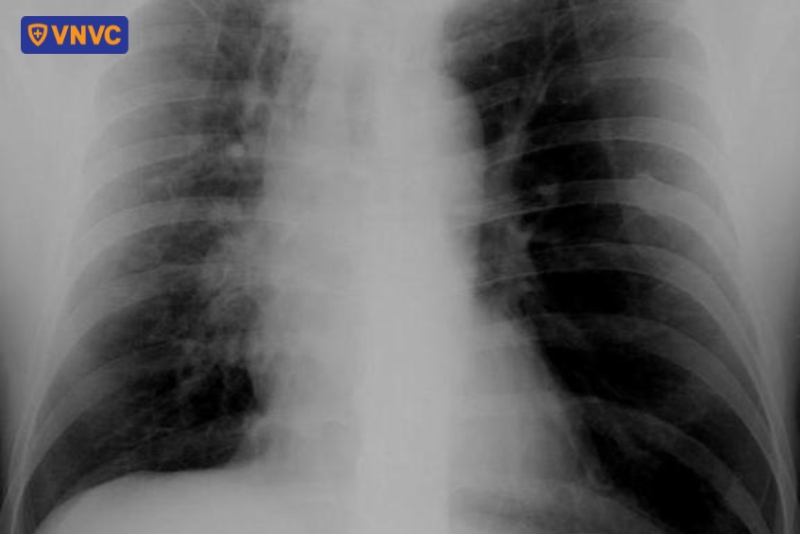

Theo chuyên gia y tế, biểu hiện thường gặp nhất của khối u vùng rốn phổi là sự tăng đậm độ ở vùng rốn phổi. Do đó, hiện tượng rốn phổi đậm có thể đến từ nguyên nhân mắc bệnh lý ác tính, chủ yếu do phì đại hạch bạch huyết hoặc khối u vùng trung tâm phổi. Thường gặp nhất là ung thư phổi nguyên phát, đặc biệt các khối u trung tâm xâm lấn hoặc di căn đến hạch rốn phổi, làm vùng này tăng đậm độ.